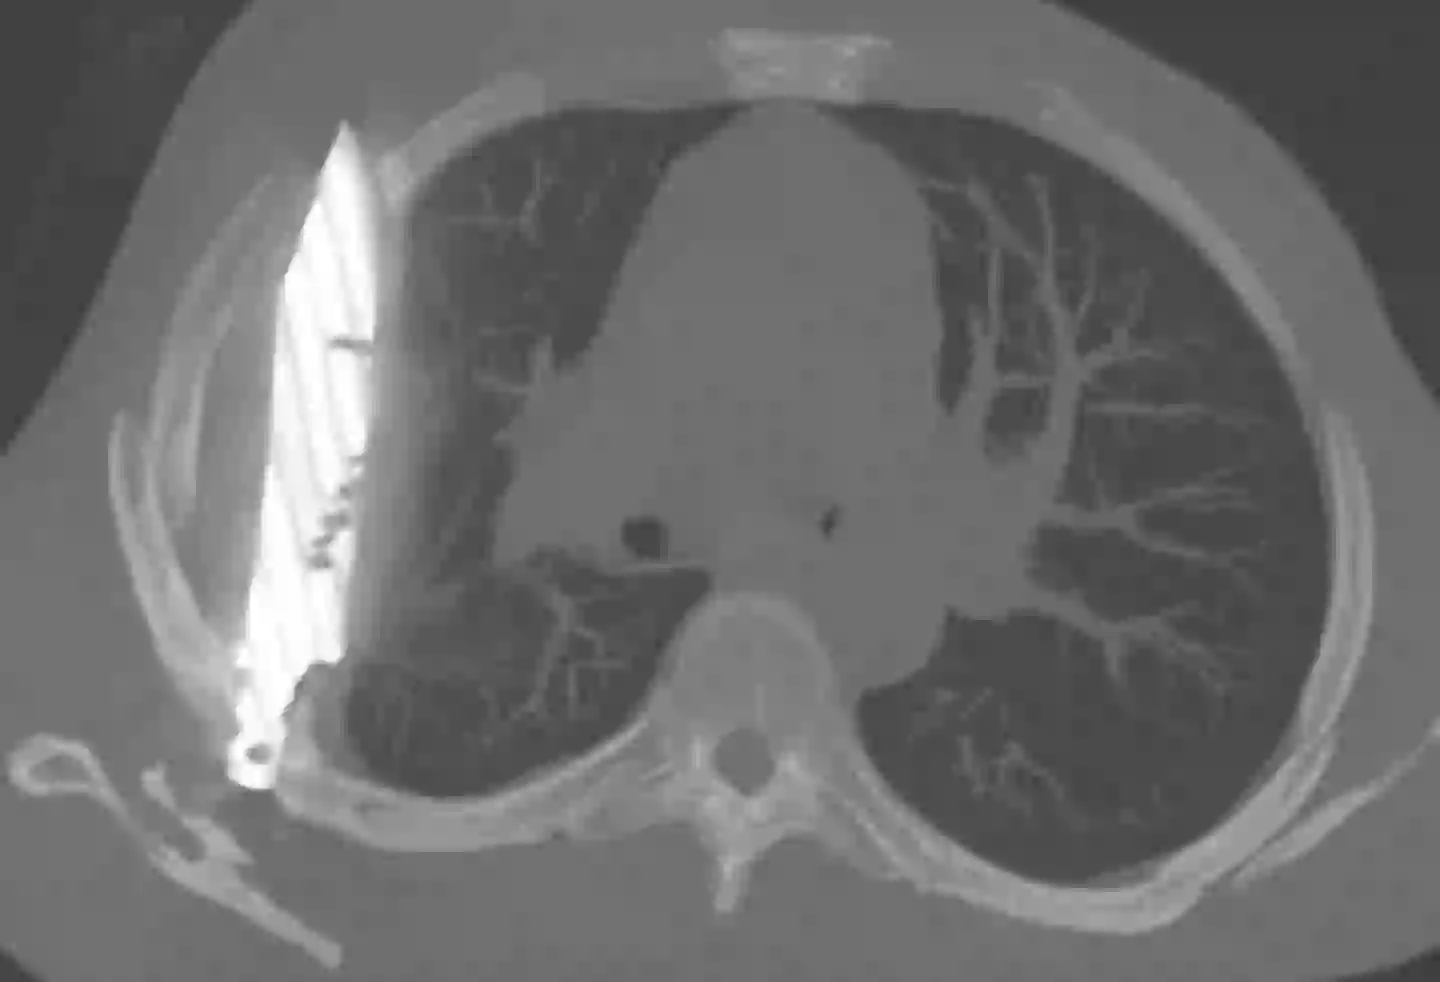

After ordering an X-ray, a ‘retained metallic object’ was found, and medics realised it was a knife, and it was surrounded by ‘pus and necrotic tissue’.

It had entered his body through his right shoulder.